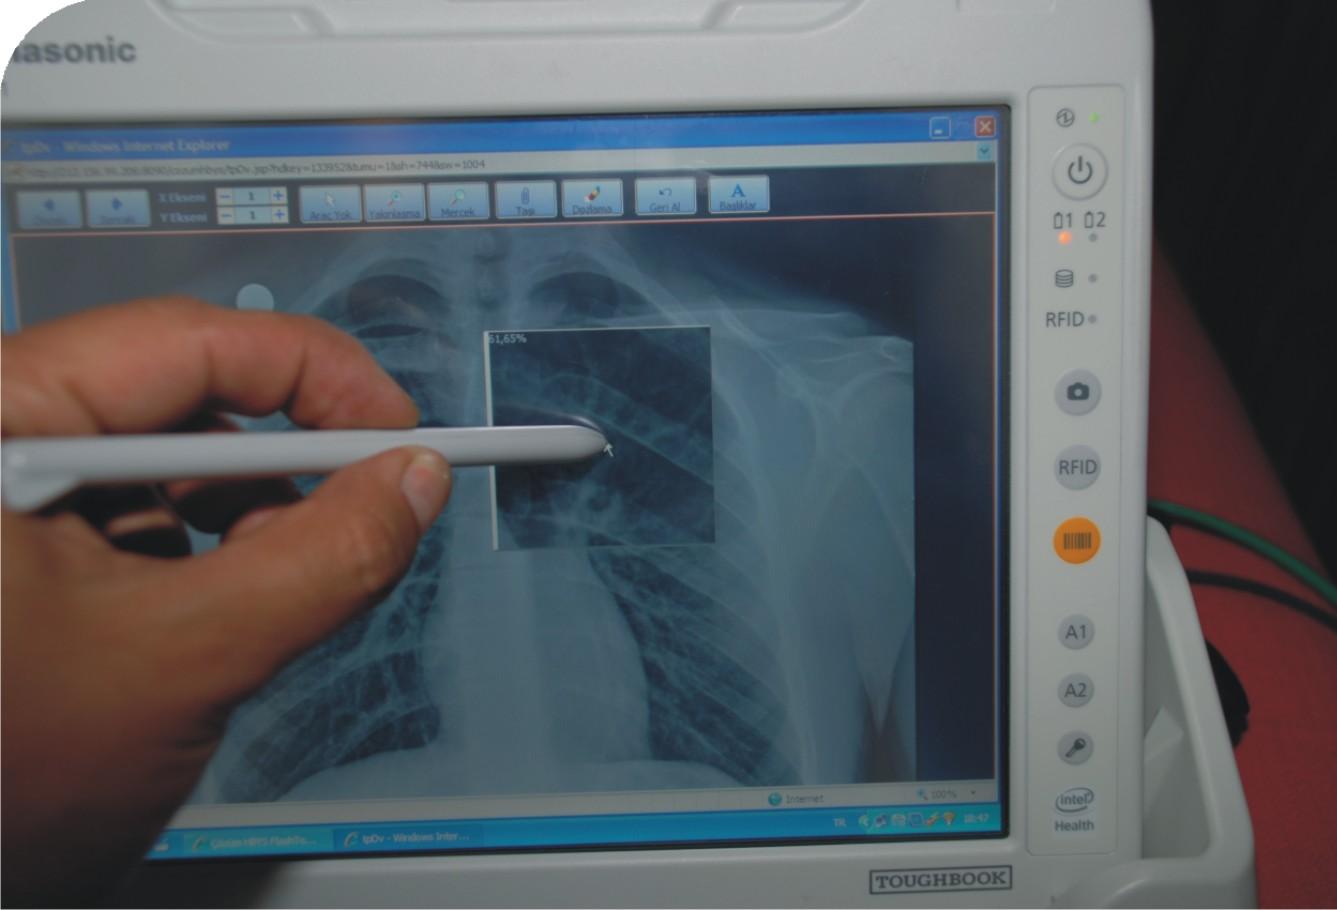

Kliniğimizde Cisco'nun yürüttüğü kablosuz internet alt yapı çalışmaları tamamlandı. Yaptığımız araştırmalar sonucunda Panasonic'in hastane ortamları için yeni geliştirdiği Intel atom işlemcili CF-H1 ürününü ve üzerindeki Çözüm Medikal Asistan yazılımını tercih ettik.

Hastanelerde, zaman kavramının çok kritik olması nedeniyle hastanın işlemlerinin zaman kaybetmeden, hızlı ve doğru bir şekilde yapılması büyük önem taşıyor. Veri kaybının önlenmesi, her uygulamanın, her isteğin, her verinin kaydedilmesi ve anında ulaşılabilmesi gerekiyor. Hataya tolerans göstermeyen sağlık alanımızda daha kaliteli ürün ve hizmete ihtiyaç duyuyoruz. MKA, bize bu imkanı sağlıyor. Mobil veri girişi ile hasta teşhis, tedavi ve takip süreçlerimizi elektronik ortama taşıyarak, elektronik sağlık kayıtlarının (ESK) daha hızlı girilmesini ve hastanın başucundan gerçek zamanlı sorgulanmasını sağlıyoruz. Hastaya ait işlemlerin takip edilmesi ile birlikte klinik işlemlerimizi de güçlendiriyoruz.

MKA ile, hekimlerimiz ve hemşirelerimiz sağlık kuruluşları içerisinde kendi masalarına bağlı kalmaksızın HBYS'ye anında ulaşabiliyorlar. Bu proje kapsamında, yatan hastalara, özel hasta numarasını içeren RFID çipli ya da barkodlu bilek bandı takılıyor. Böylelikle hekimler ve hemşireler, RFID ve barkod okuyuculu MKA'ları kullanarak hasta hakkında gerekli bilgilere, günlük rutin kontrolleri sırasında, hastanın yanındayken dahi ulaşabiliyorlar.

MKA ile, hasta tedavilerinin kolayca planlanabilmesi, izlenebilmesi ve tüm sonuçların evraksız bir şekilde değerlendirebilmesini sağlıyoruz. Böylece, kağıt ve kalem kullanımını ciddi ölçüde azaltılıp, doğru teşhis ve tedavi oranını artırırken, tıbbi hata yapma olasılığını da en alt seviyeye indiriyoruz.